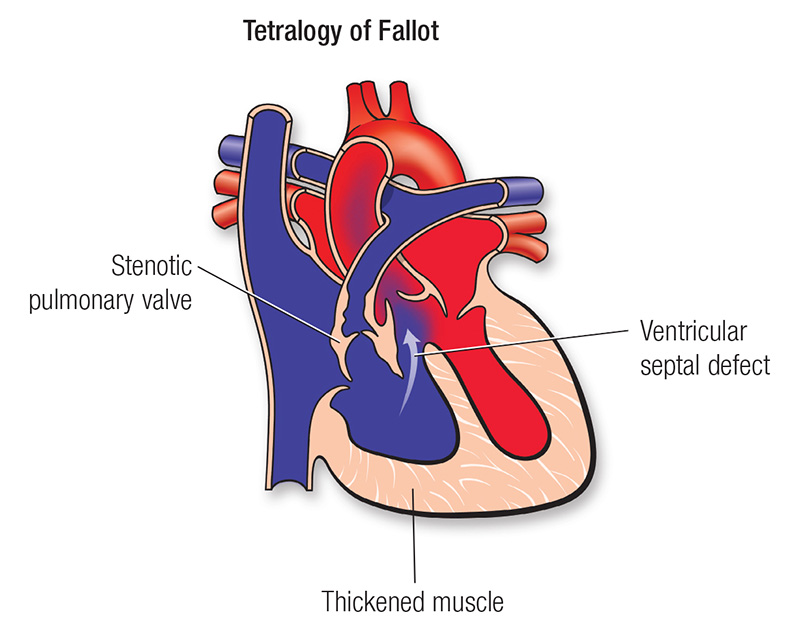

Overview

Package includes:

Days in hospital : 10 to 11 Days (For patient and one attendant)

Days in hotel : 14 Days (For patient and one attendant)

Room type in hospital : Shared

Room type in hotel : Private

Hotel category: Standard

Value added benefits of the TOF treatment: